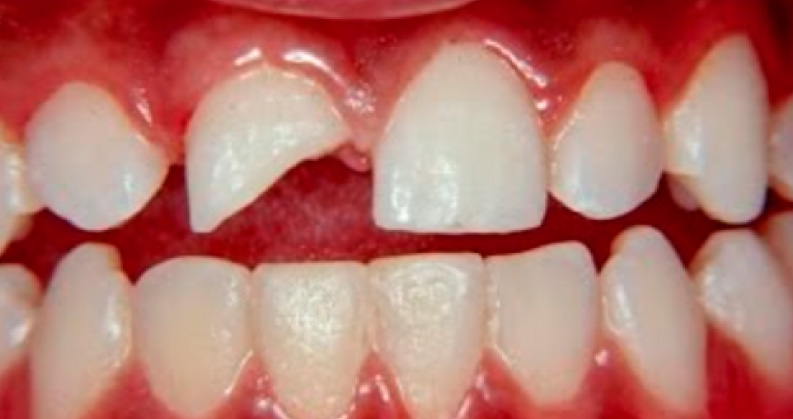

Desde uma simples trinca, fratura ou até a completa avulsão (saída completa) do dente.

Trauma de concussão Fratura de parte da coroa dentária Frantura da raíz no Raio-x

Outra alternativa é manter em soro fisiológico ou leite e procurar imediatamente seu dentista. Se for apenas uma fratura, fazer o mesmo, pois o fragmento de dente poderá ser colado pelo dentista.